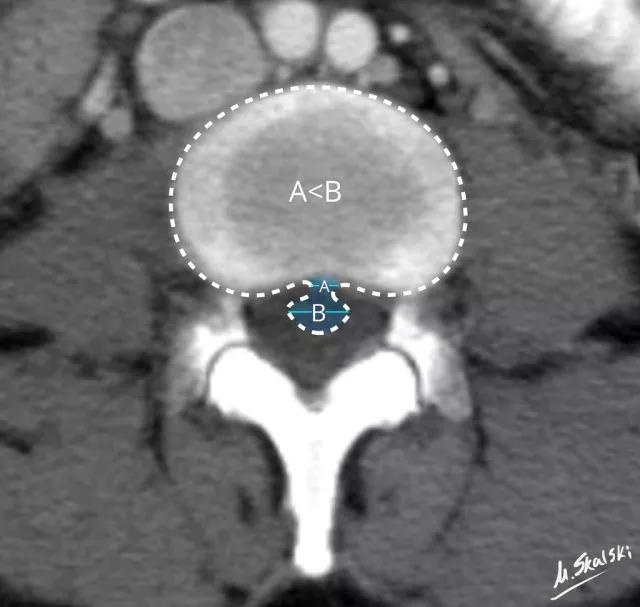

3. 椎间盘脱出(Disc extrusion)

纤维环、后纵韧带完全破裂,髓核突入椎管内。

图 5 椎间盘突出的影像学定义为突出椎间盘的基底部(A)<突出组织的直径(B)